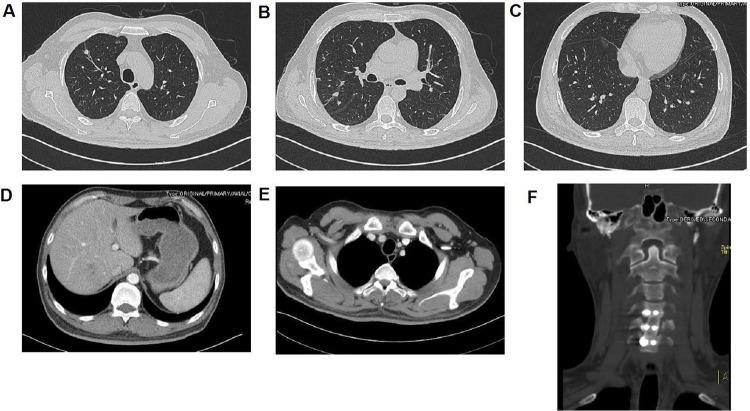

() is a causative pathogen of some rare diseases such as primary atrophic rhinitis and ozena. Here, we describe one case of a potentially lethal kind of infection in which multiple organs were implicated. A 40-year-old diabetic male patient presented to our hospital due to fever with right anterior chest mass and neck and shoulder pain for half a month. Based on all examination results, he was diagnosed with sepsis, bilateral pulmonary/right chest wall/liver abscesses and 5th cervical vertebra bone destruction with prevertebral abscesses, all related with infection. During the first time of admission, he was treated with antimicrobials without operations. Twelve days after his first discharge, fever and pain occurred again, the patient was treated with antimicrobials, operations (anterior debridement, spinal canal decompression, iliac bone graft fusion and internal fixation) and rehabilitation at second admission. The patient recovered well and was discharged from hospital. This case report demonstrates that can trigger a wide range invasive infections. Particularly, 5th cervical vertebra bone destruction was first reported as a clinical manifestation of infection in our patient.

()是一些罕见疾病如原发性萎缩性鼻炎和臭鼻症的致病病原体。在此,我们描述一例涉及多个器官的潜在致命性感染病例。一名40岁的糖尿病男性患者因发热伴右前胸肿块以及颈部和肩部疼痛半个月前来我院就诊。根据所有检查结果,他被诊断为脓毒症、双侧肺/右胸壁/肝脓肿以及第5颈椎骨质破坏伴椎前脓肿,所有这些均与()感染有关。首次入院时,他接受了抗菌药物治疗,未进行手术。首次出院12天后,发热和疼痛再次出现,患者在第二次入院时接受了抗菌药物治疗、手术(前路清创、椎管减压、髂骨植骨融合及内固定)和康复治疗。患者恢复良好并出院。该病例报告表明()可引发广泛的侵袭性感染。特别是,第5颈椎骨质破坏作为()感染的临床表现首次在我们的患者中被报道。